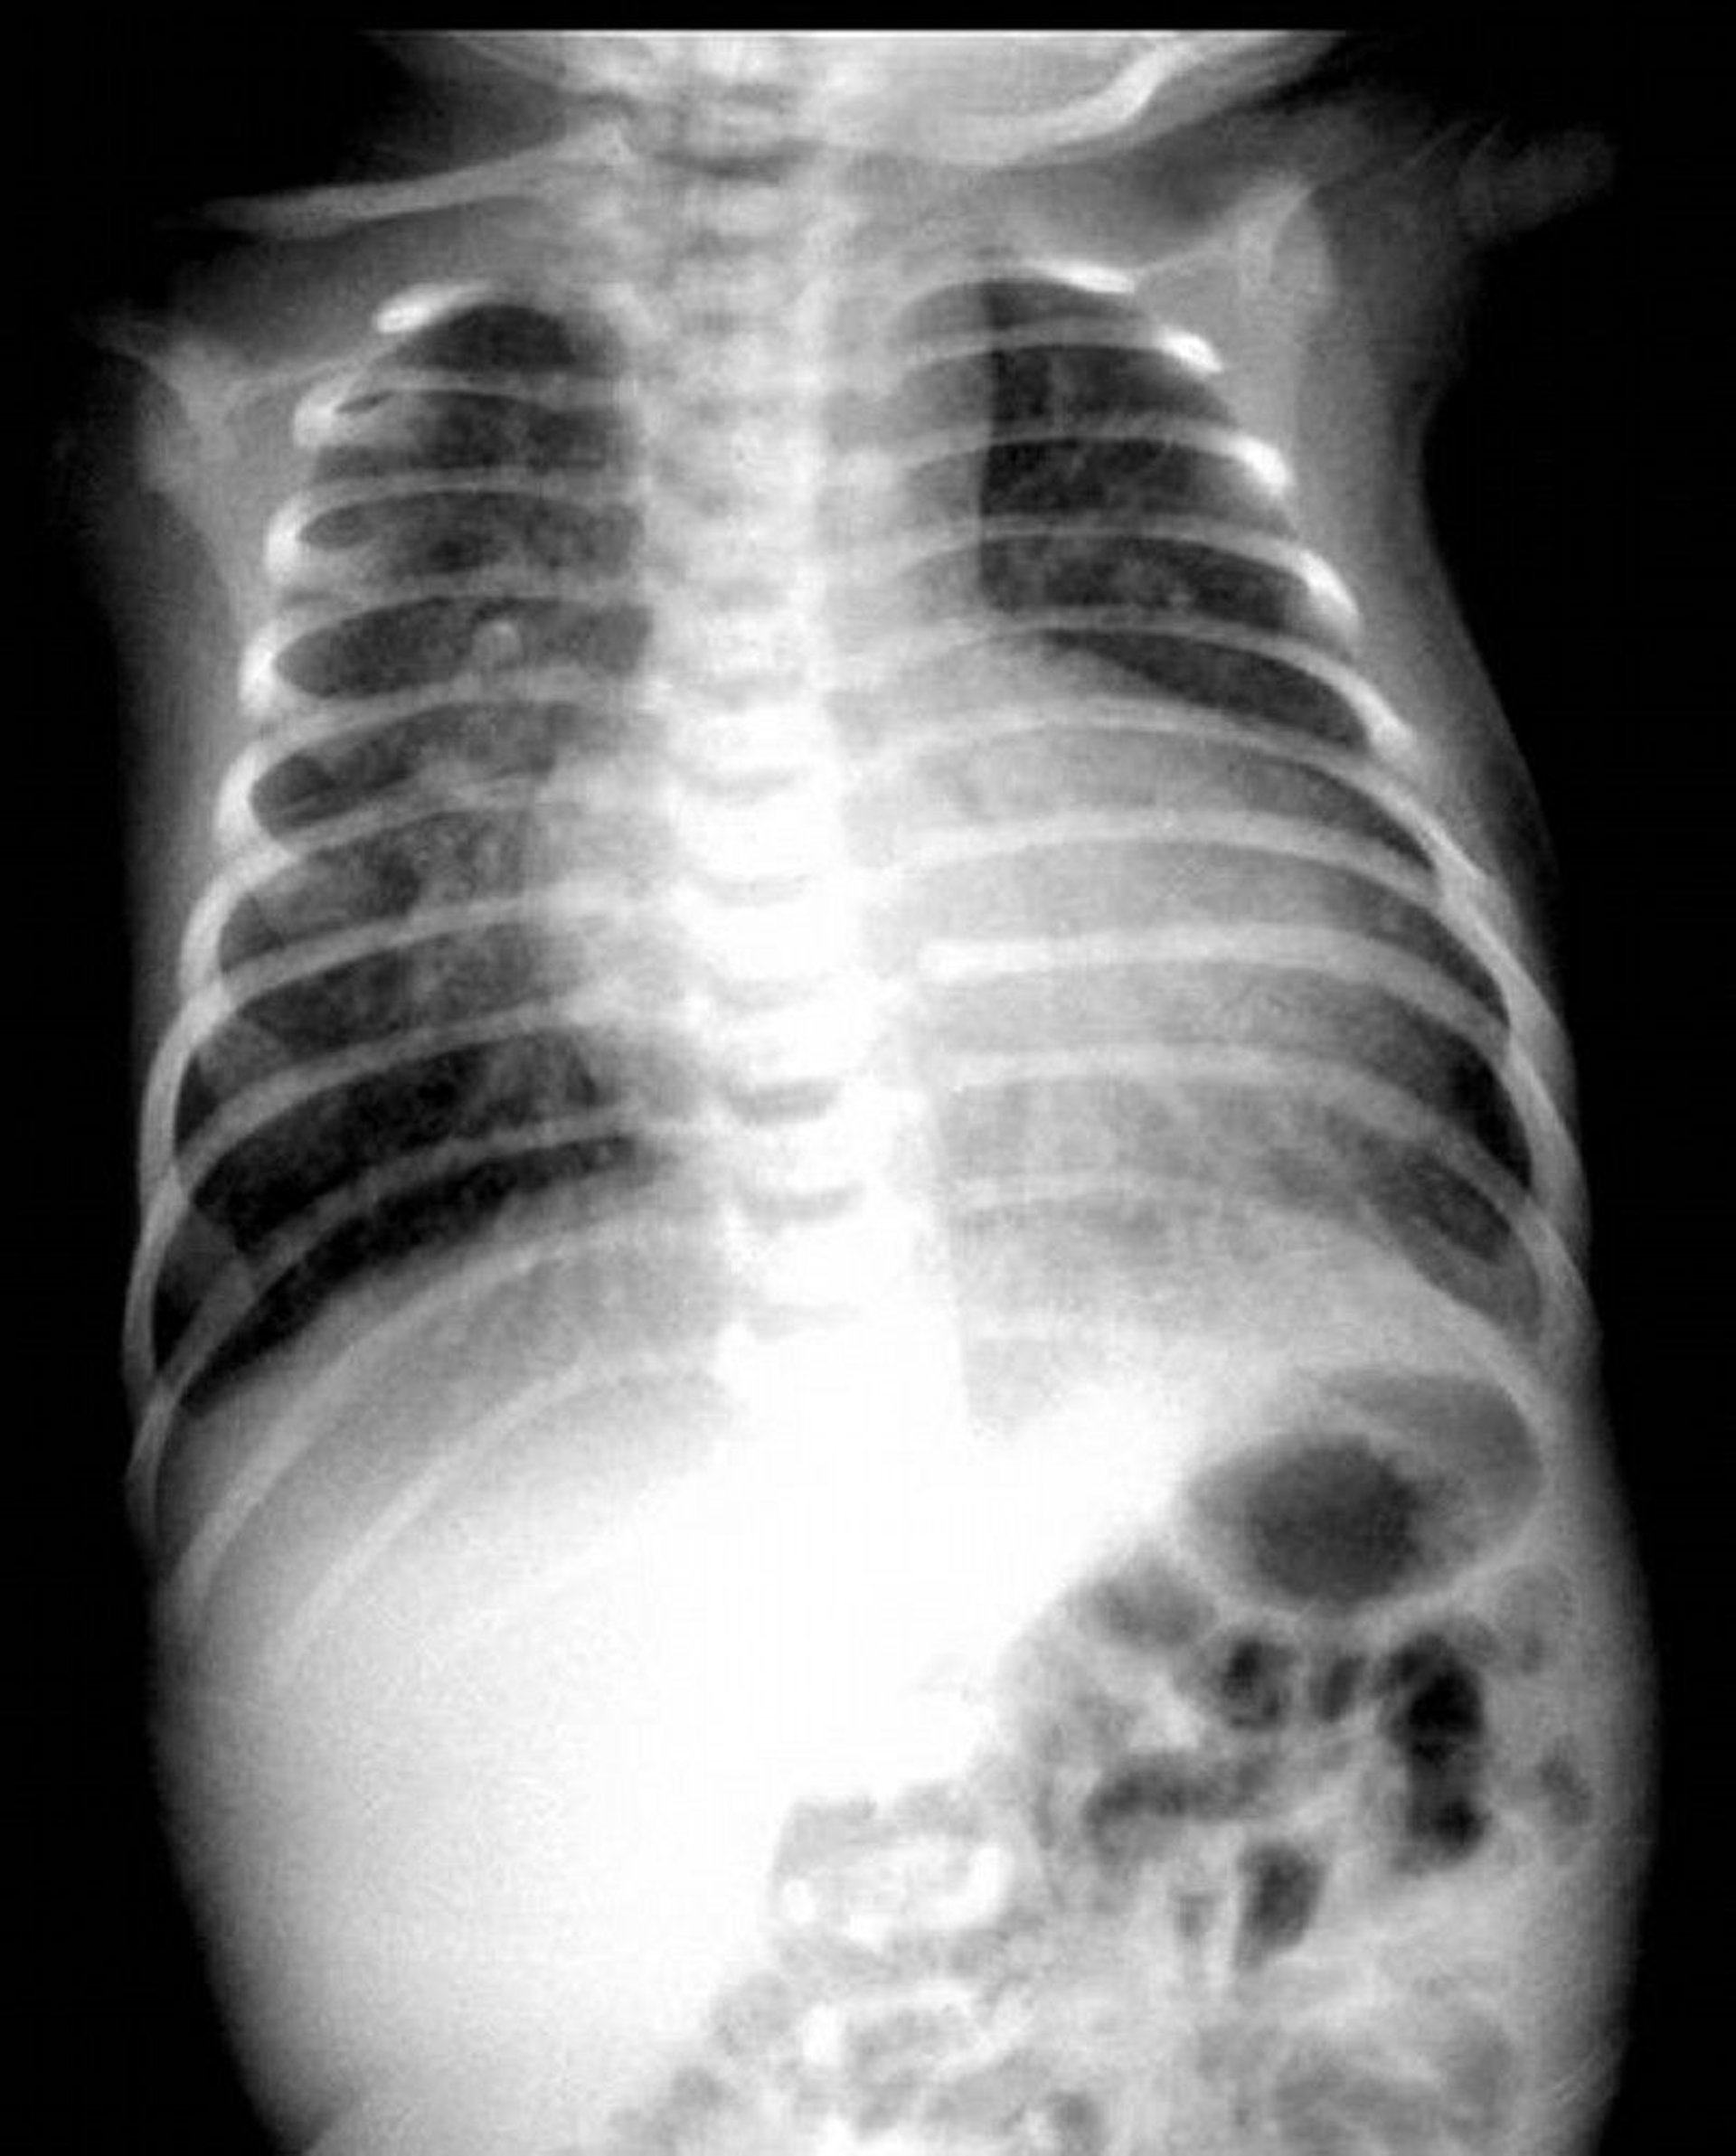

Chest x-ray showing classic egg-on-a-string appearance in a patient with transposition of the great arteries.